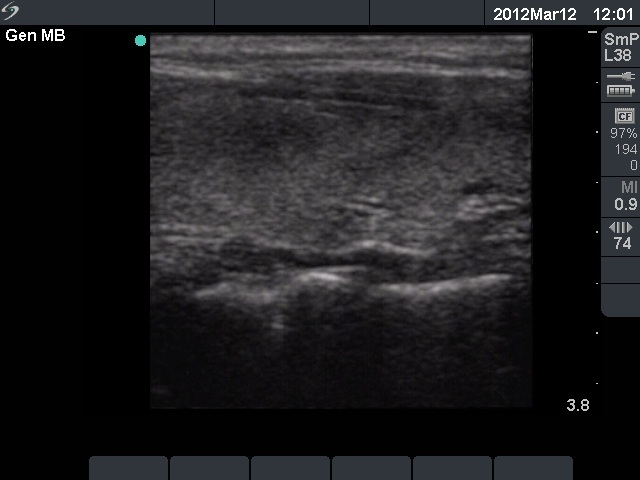

Initial examination (first row of images):

Clinical presentation: A 29-year-old woman requested a second opinion. She was in the 11th week of her pregnancy. She had mild neck discomfort for 2 months. A suspicious nodule was found in the left lobe on the evaluation. Aspiration cytology was repeatedly non-diagnostic. She was told that she had thyroid carcinoma with great probability. Her endocrinologist recommended to abort the child and then to undergo thyroidectomy.

Palpation: The left thyroid was hard on palpation, but not painful.

Ultrasonography: The right thyroid was echonormal and contained several small, insignificant lesions. There was a hypoechogenic lesion with blurred borders in the central and in the ventro-medial part of the left thyroid with increased intranodular blood flow.

Aspiration cytology resulted in thyroiditis, not otherwise specified.

Laboratory tests: subclinical hyperthyroidism. Serum-calcitonin, anti-TPO, anti-hTg, TSAb resulted in normal values.

Combined clinical-sonographic-cytological diagnosis: subacute, de Quervain's thyroiditis.

Suggestion: regular follow-up examinations.